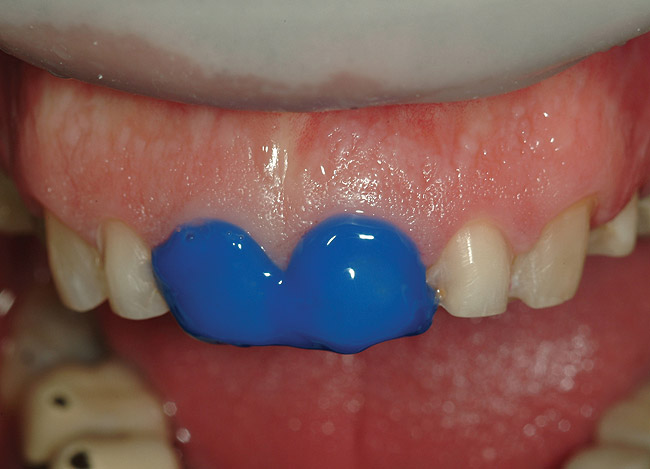

Figure 31  Etch was applied to teeth Nos. 8 and 9.

Figure 31

Figure 32  View of the bonded IPS e.max restorations on the 10 upper anterior teeth

Figure 32

Seating the Restorations